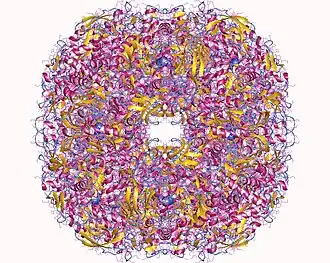

Proteom Helicobacteru pylori byl systematicky studovaný a celkově 70 % všech bakteriálních proteinů bylo detekováno hmotnostní spektometrií. Téměř polovina proteomu byla kvantifikována, což naznačuje velký počet kopií proteinů v typické bakteriální buňce.[28]

Studie na bakteriální interaktomu – schématu všech molekulárních interakcí ve specifické buňce – prokázala více než 3000 interakcí mezi jednotlivými proteiny. Při studii se zkoumaly jak proteiny ve stabilní formě, tak proteiny v takzvané dynamické formě, která určuje funkci proteinu v buňce. Kolem 1500 proteinů u Helicobacter pylori zůstalo v květnu 2018 s neobjasněnou buněčnou funkcí.[29]